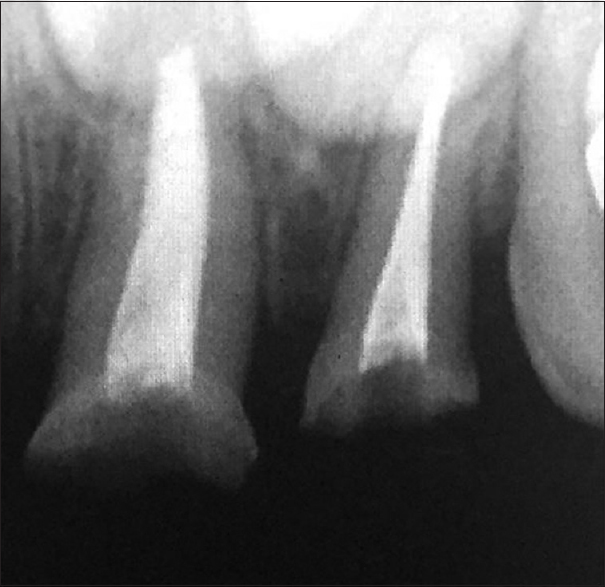

Two-third of the obturation material was removed from the upper left central and lateral incisors [Figure 3]. The trial fit of the endodontic post was done. On confirming the appropriate fit of the post, they were then conditioned with 37% phosphoric acid for 30 s, followed by washing, drying, and applying the adhesive system followed by cementation with resin-reinforced glass-ionomer cement. The shape and shade of the biological post and crown were modified to match the adjacent right central and lateral incisors, respectively. The parents were satisfied with the rehabilitation of the teeth using biological restoration [Figure 4].

thumb

Figure 3: Postspace preparation